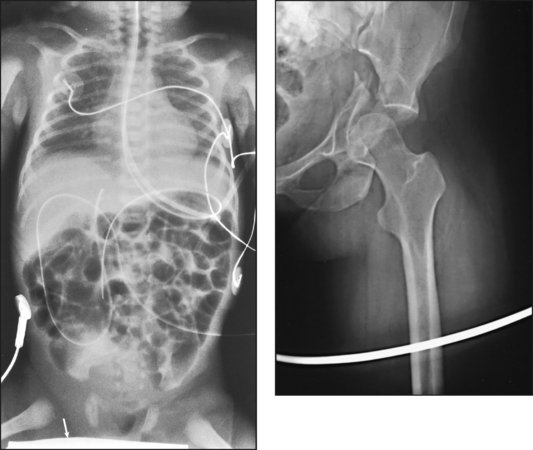

Fig. 28-3 Mobile radiograph of proximal femur and hip, showing comminuted fracture of left acetabulum. A, Poor-quality radiograph resulted when grid was transversely tilted far enough to produce significant grid cutoff. B, Excellent-quality repeat radiograph on the same patient, performed with grid accurately positioned perpendicular to central ray.